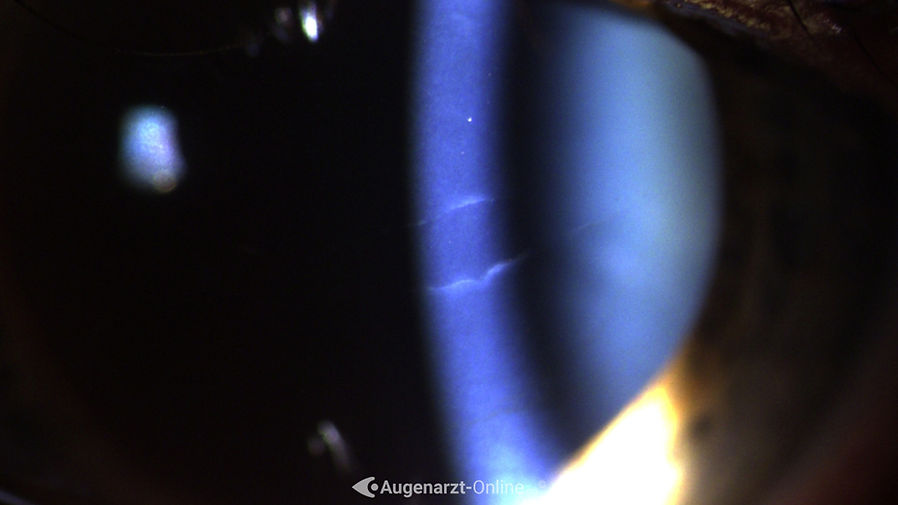

Haab'sche Linien

Zufallsbefund einer Ruptur der Descement Membran (Haab'sche Stria). Kein Trauma erinnerlich, kein vorausgegangener Glaukomanfall.

Spaltlampenfoto

| Ⓒ 2021

Foto einer Ruptur im Bereich der Descementmembran der Hornhaut (Haab's striae)